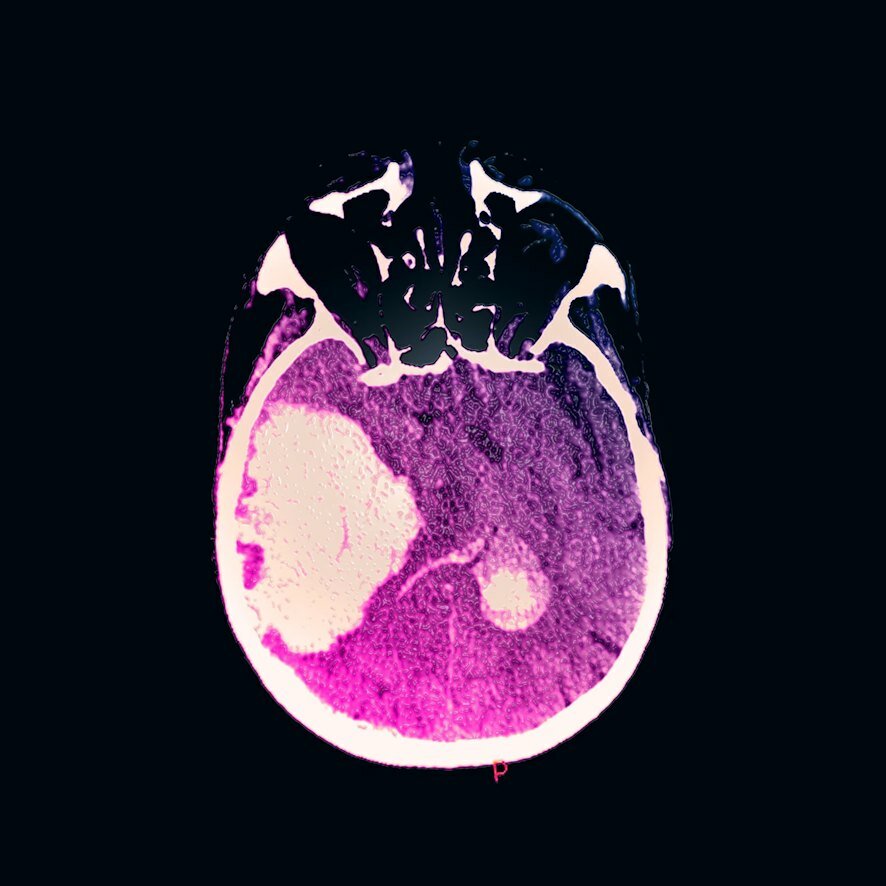

Международное исследование, опубликованное в авторитетном журнале Neurology, показало тревожную взаимосвязь между регулярным употреблением алкоголя и тяжестью геморрагических инсультов. Согласно полученным данным, люди, потребляющие три и более дозы* алкогольных напитка (Более 150 гр водки) в день, сталкиваются с кровоизлияниями в мозг в среднем на 11 лет раньше, чем умеренно пьющие или трезвенники.

- Объем внутримозговых кровоизлияний был значительно больше

- Повреждения мозга оказывались более обширными

- Уровень смертности был выше